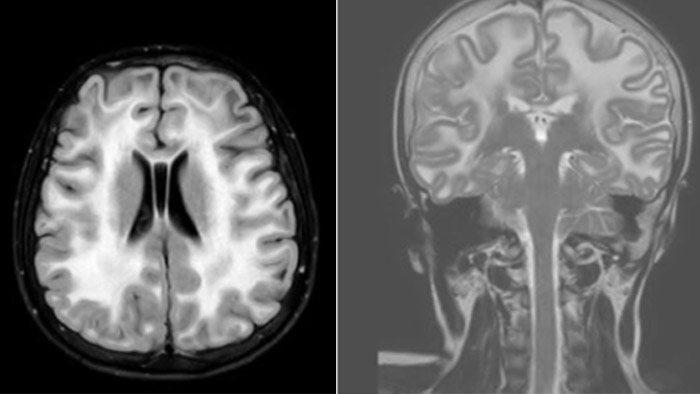

Hydrocephalus post hemorrhagic Both pictures show a ventriculoperitoneal shunt. With our previous scanner our hydrocephalus protocol needed about 25 min. With Ambition the examination time is about 14 min. including a CSF PCA sequence to show flow in the aqueduct.

Leukodystrophy in a teenager

Rostral meningitis and arachnoiditis Both images are from the same 3D T1-weighted post contrast sequence in a newborn, under treatment.